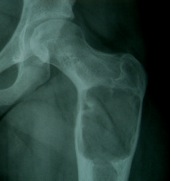

X-ray

Well-defined lucency

- thin sclerotic rim

- usually central

- thinned cortex with slight expansion

- thin internal septa

- can be multi-loculated

Fallen-Leaf (AKA fallen-fragment)

- with pathological fracture

- indicates that the lesion has no matrix and is fluid filled

Fallen leaf sign

DDx ABC

ABC

- eccentric (v central)

- width > physis

- can be very difficult to tell

- requires biopsy